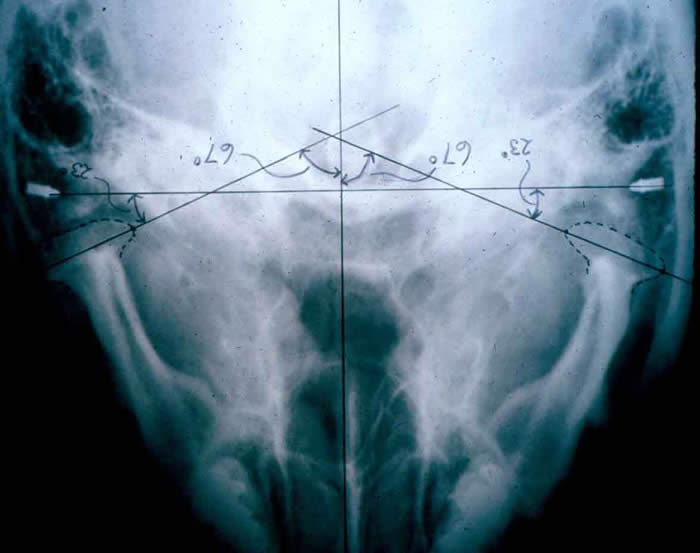

Submental-vertex View

This projection allows measuring the angle of the condyles to the mid-sagittal plane. It is often used as a scout film prior to taking corrected tomograms, thus permitting accurate sectioning of the condyles perpendicular to their individual long axes.